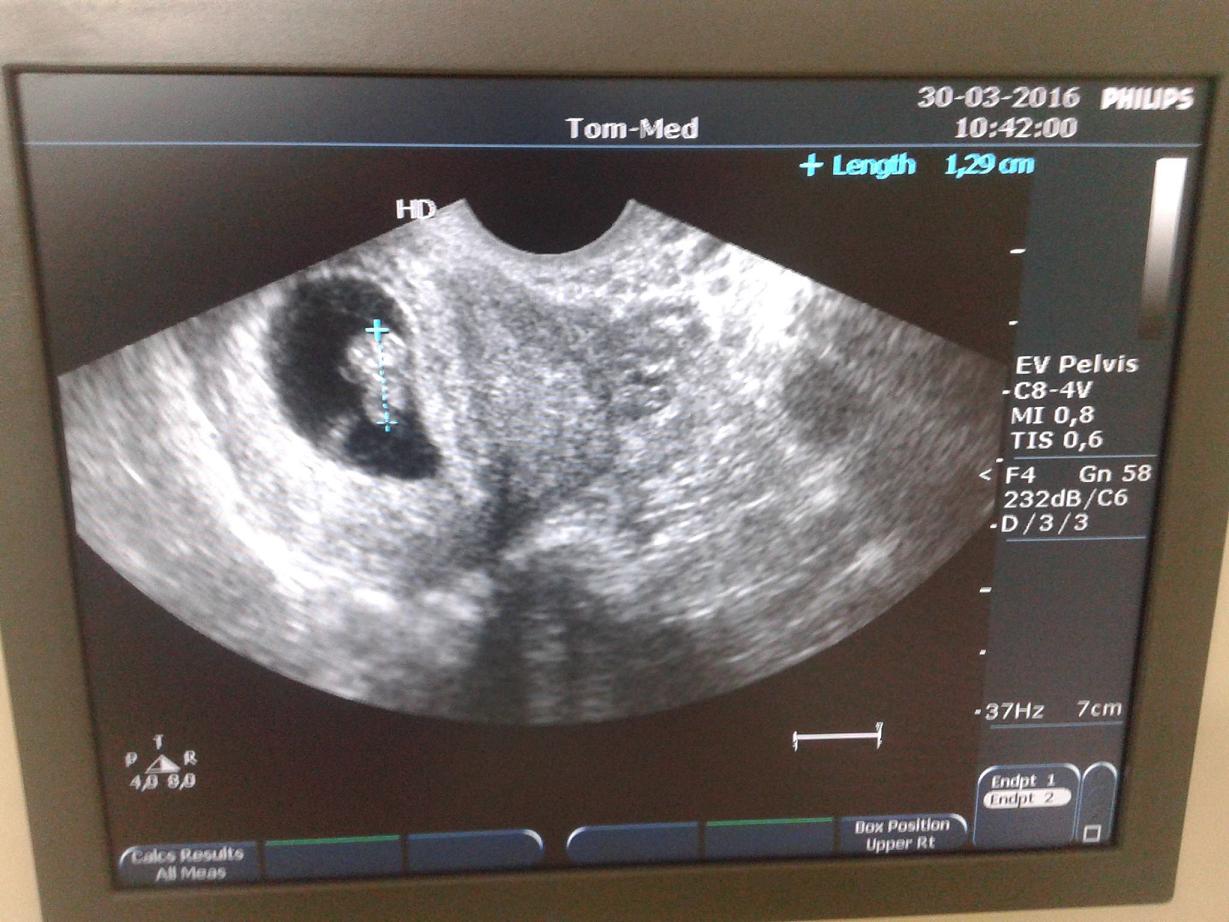

Udało mi się w przychodni ktorej jestem prywatnie zarejestrowana przelozyc usg z 10.05 na jutro na 13.40 wiec zobacze co od piatku zmienilo sie u mojego malenstwa! Tak sie ciesze!!!

Jestem w domciu pomniejszylam zdj. Wzruszylam sie z mezem :) Dziewczyny mi sie wydaje ze dzidziolek macha mi <3 Jestem zakochana <3